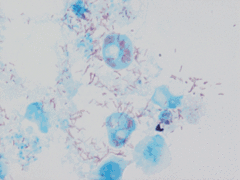

Description de l'image Rickettsia conorii in Vero.gif.

Rickettsia conorii est une bactérie Gram-négative intracellulaire obligatoire.